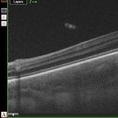

AZOOR

Sep 25 2025 by Hemanth Murthy, MBBS, MD, FASRS

OCT image of right eye of a 72 yr male with history of progressive loss of vision and loos of field of vision more in right eye. It shows a tribunal pattern of outer retina loss

Photographer: Mr Veda Vyas

Condition/keywords: acute zonal occult outer retinopathy (AZOOR)